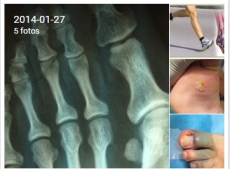

El doctor Felipe Basas afirma que es fundamental realizar revisiones periódicas en los niños para detectar cualquier patología (GALERÍA DE FOTOS)

En Clínica del Pie Basas tratan a pacientes de todas las edades, ofreciendo la información que necesitan para tomar buenas decisiones sobre su pie. Podología deportiva, tratamiento del pie diabético, eliminación definitiva de callos, cirugía en juanetes, fascitis, dedos en garra, uñas incarnadas o espolones son algunos de los servicios que realizan en esta clínica, una referencia en Salamanca.

Teniendo en cuenta que más del 75 por ciento de las personas experimentarán problemas de los pies en un momento u otro en su vida, es fundamental mantenerlos en perfecto estado. Sin embargo, el cuidado de los pies debe empezar desde la infancia. El doctor Basas explica que los padres llevan a sus hijos periódicamente a las revisiones del pediatra, "pero también es necesario revisiones del podólogo para detectar si un pie puede tener una patología en el futuro y para asegurar un correcto crecimiento".